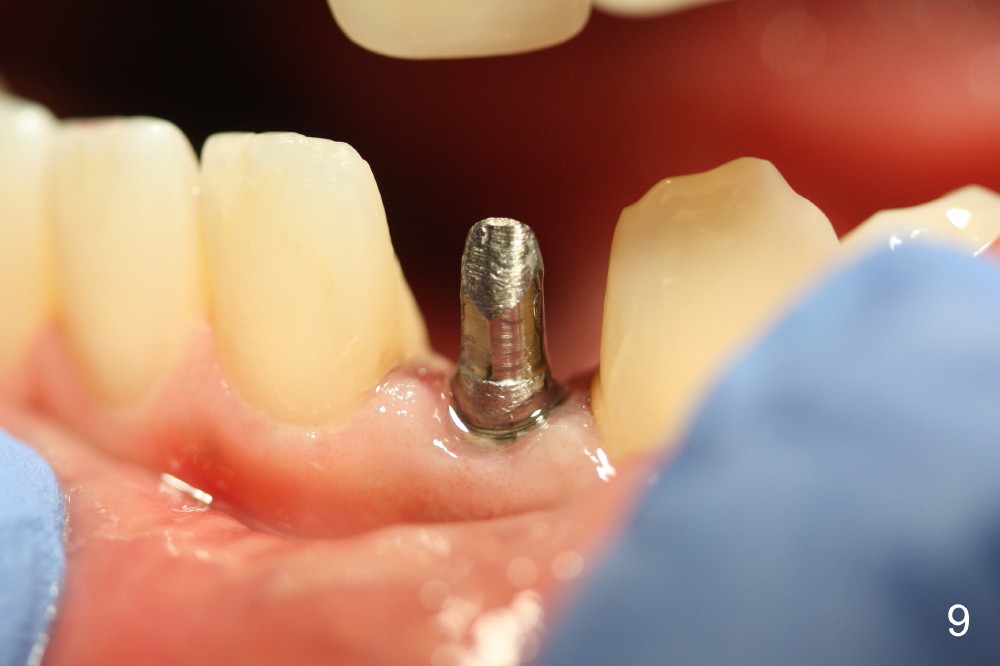

Within the first several days postop, the patient reports mild tenderness from one of the neighboring teeth.  Otherwise she is doing fine.  Again due to finance, she does not return for restoration for more than 1 year.  PA taken 10 months postop shows that there is no abnormality (Fig.7).  In fact bone resorption occurs gradually over 2 years 2 months postop, manifested as the 1st thread supracrestal (Fig.8 <).  When the 1-piece implant is reprepped for impression 2 years 2 months postop, the micro threads are found apical to the prep margin (Fig.9).  The nervous patient has had occasional tooth sensitivity 5 years postop.  A narrower implant is more suitable for this case (2.0 or 2.5 mm).